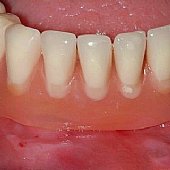

• Darstellung des Kieferkammes eines zahnlosen Unterkiefers.

• Versorgung mit 5 Implantaten zur Aufnahme der festsitzenden Unterkieferbrücke.

• Die fertige fest sitzende Brücke im Unterkiefer.